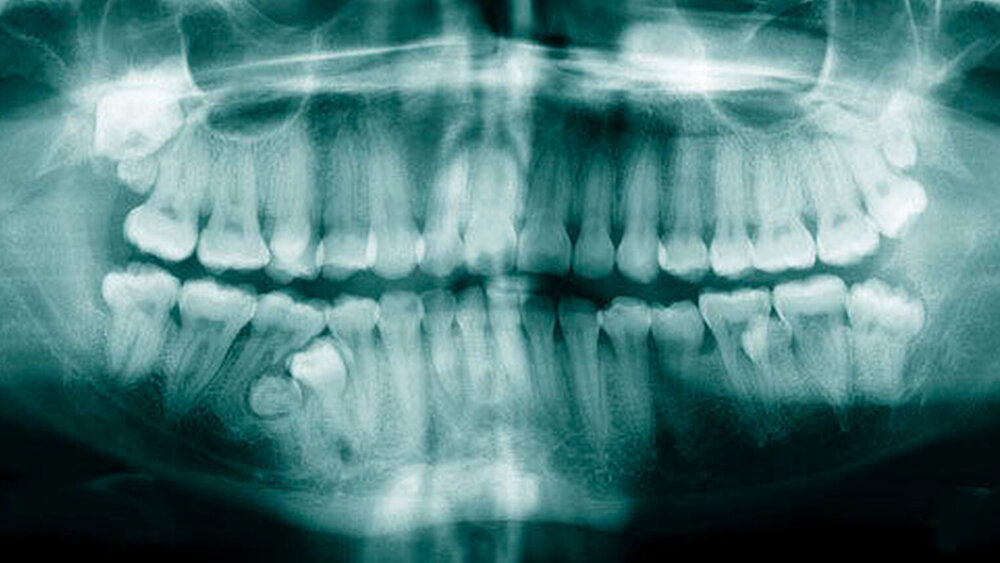

Die Prävalenz überzähliger Zähne wird im Bereich von 0,07 Prozent bis 0,6 Prozent für das Milchgebiss [Luten, 1967; Ravn, 1971; Järvinen Lehtinen, 1981; Magnússon 1984; Skrinjari Barac-Furtinovi, 1991; Yonezu et al., 1997; Chen et al., 2010] und von 0,3 Prozent bis 3,2 Prozent für die bleibenden Zähne [Luten, 1967; Bäckman Wahlin, 2001; Salcido-García et al., 2004; Leco Berrocal et al., 2007; Gündüz et al., 2008; Yagüe-García et al., 2009; Schmuckli et al., 2010; Fardi et al., 2011] angegeben. Die Mehrheit der überzähligen Zähne im Milchgebiss sind seitliche Schneidezähne im Oberkiefer, die meist mit einer normalen Morphologie und Lage durchbrechen (Abbildungen 1 bis 3) [Luten, 1967; Humerfeld et al., 1985; Garvey et al., 1999; Ferrés-Padró et al., 2009]. Der oft ungestörte Durchbruch und das Ausbleiben von Symptomen führen dazu, dass überzählige Zähne in der Milchdentition oft gar nicht diagnostiziert werden, und dies wird auch als Erklärung für die unterschiedlichen Prävalenzen überzähliger Zähne im Milch- und bleibendem Gebiss angeführt [Wang Fan, 2011]. Überzählige Zähne sind häufiger bei Männern als bei Frauen, wobei über ein Verhältnis von 1,18:1 bis 4,5:1 berichtet wird [Rajab Hamdan, 2002; Fernández Montenegro et al., 2006; Gündüz et al., 2008; Wang Fan, 2011]. In der Schweiz publizierten von Arx (1990) und Schmuckli und Mitarbeiter (2010) Geschlechterverhältnisse von 2,6:1, beziehungsweise 2,75:1. In einer aktuellen Arbeit von Mossaz und Mitarbeiter (2014) von Patienten aus dem Raum Bern lag dieses Verhältnis etwas ausgeglichener bei 1,61 zu 1.